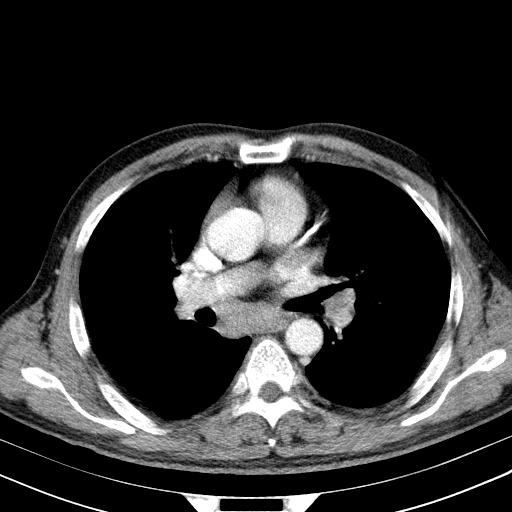

先行ct平扫,纵膈内多发软组织影,ct值约为36hu,以下为增强扫描和腹部平扫。

经典?纵膈多发肿大淋巴结。腹膜后未见异常。

淋巴瘤?胸腺瘤?

1)考虑淋巴瘤。2)双侧少量胸腔积液。